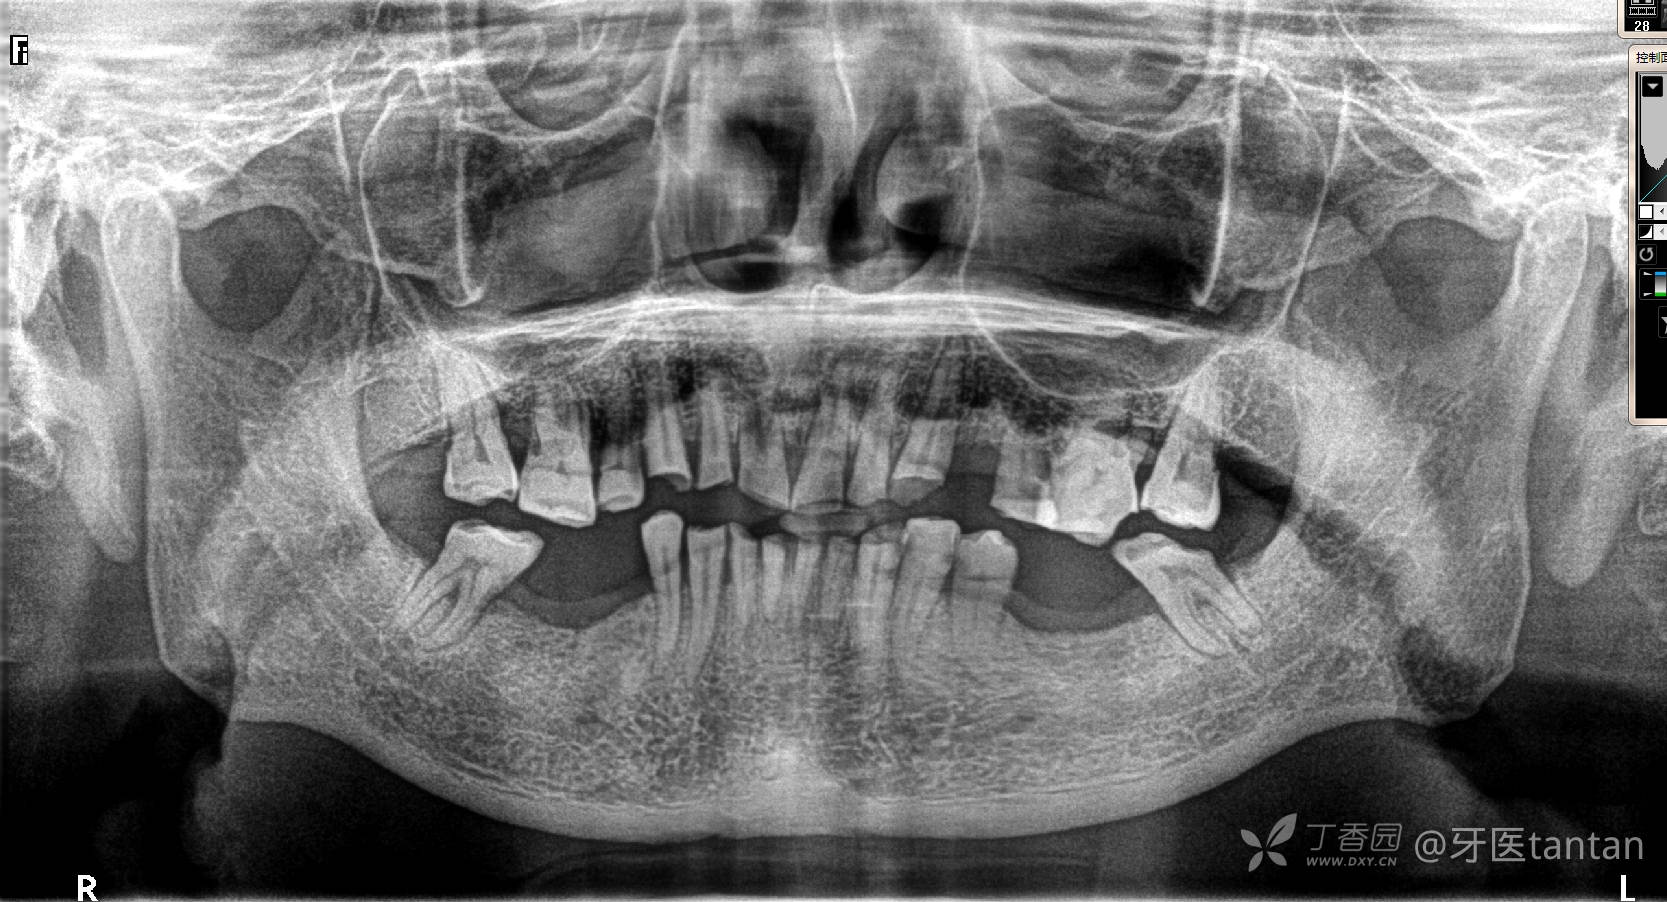

全景